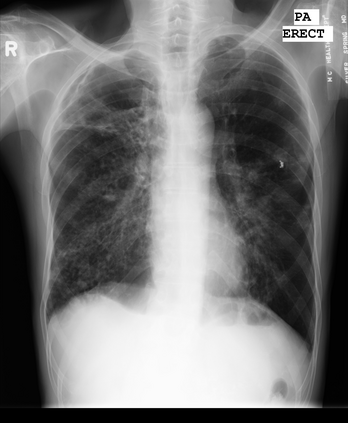

Tuberculosis remains a critical global health issue, particularly in resource-limited and remote areas. Early detection is vital for treatment, yet the lack of skilled radiologists underscores the need for artificial intelligence (AI)-driven screening tools. Developing reliable AI models is challenging due to the necessity for large, high-quality datasets, which are costly to obtain. To tackle this, we propose a teacher--student framework which enhances both disease and symptom detection on chest X-rays by integrating two supervised heads and a self-supervised head. Our model achieves an accuracy of 98.85% for distinguishing between COVID-19, tuberculosis, and normal cases, and a macro-F1 score of 90.09% for multilabel symptom detection, significantly outperforming baselines. The explainability assessments also show the model bases its predictions on relevant anatomical features, demonstrating promise for deployment in clinical screening and triage settings.